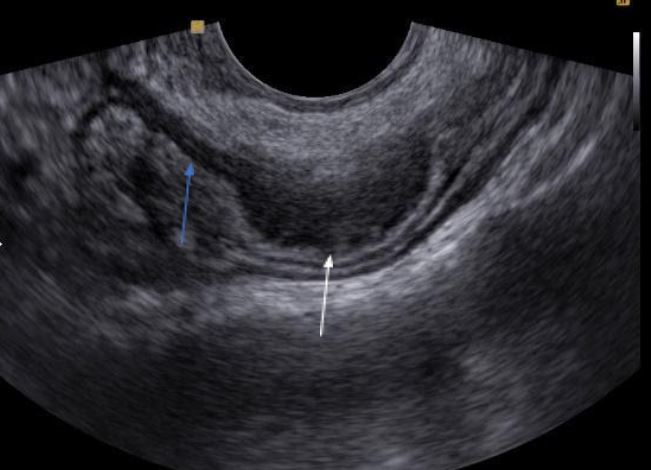

Imagem de endometriose intestinal. A seta branca indica a musculatura da alça intestinal espessada por endometriose. A seta azul indica a musculatura alça intestinal com espessura normal.

Endometriose no intestino

A endometriose intestinal é definida quando a doença atinge a camada muscular de algum segmento do intestino.

Locais mais comuns da endometriose intestinal:

- Reto 67%;

- Sigmoide 18%;

- Apêndice 6%;

- Íleo 5%;

- Ceco 4%.

O sintomas específicos da endometriose intestinal é a dor para evacuar durante a menstruação, podendo estar acompanhada de diarreia ou constipação.

O diagnóstico de endometriose intestinal é melhor pelo ultrassom transvaginal, devido a melhor capacidade de definição anatômica da estratificação do intestino e pelo fato do movimento das alças gerar artefatos na ressonância magnética que podem atrapalhar a interpretação do exame.